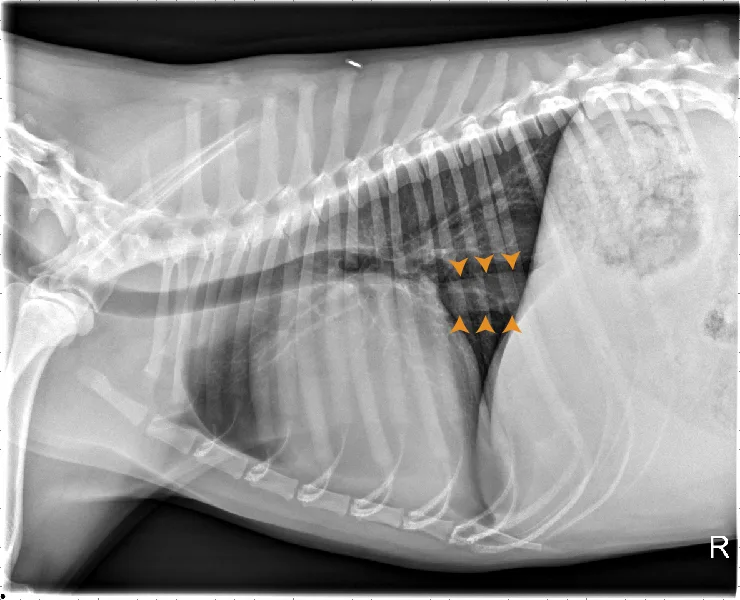

At least 2 orthogonal views, ideally taken during peak inspiration, are necessary for appropriate radiographic study of the cardiovascular system; however, a 3-view study is ideal for comprehensive evaluation of the thorax. Some differences should be considered when deciding to acquire a right versus left lateral projection and a dorsoventral (DV) versus ventrodorsal (VD) projection. On the left lateral view, the cardiac silhouette is typically more rounded and the apex is further elevated from the sternum than in the right lateral view (Figure 1). In the DV view, the cardiac silhouette is commonly displaced cranially and to the left by the diaphragm and appears more rounded than in the VD view. The caudal pulmonary vasculature is better delineated in the DV view, whereas the lung field (particularly the accessory lobe) is better evaluated in the VD view (Figure 2).

FIGURE 2 Normal DV (left) and VD (right) projections of the thorax in a large, crossbreed dog. The cardiac silhouette appears more rounded, and the caudal pulmonary vasculature is more apparent (arrowheads) in the DV view compared with the VD view. In some DV projections, the cardiac silhouette can appear significantly displaced to the left (not apparent in this case). Images courtesy of Federico Villaplana Grosso, DACVR, DECVR